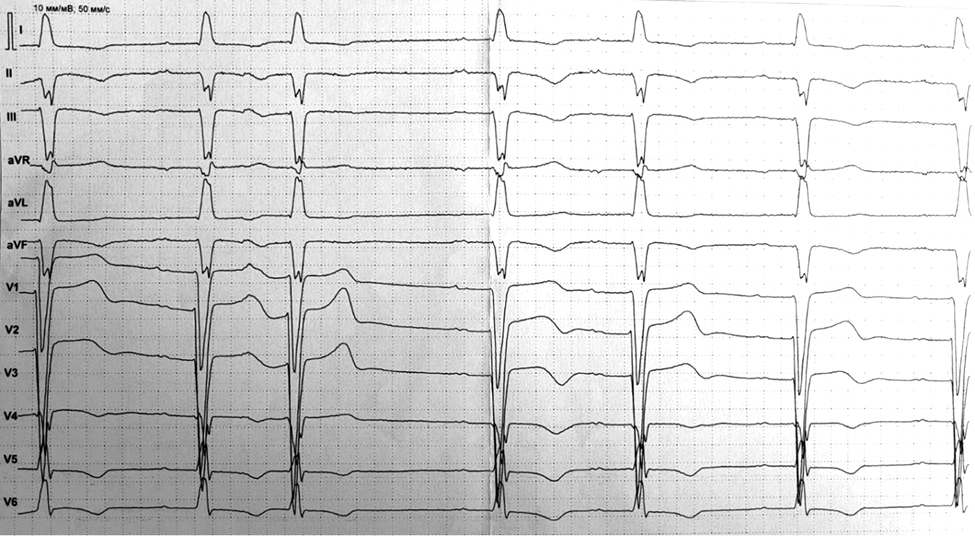

При поступлении в стационар состояние удовлетворительное, аускультативно выслушивались короткие пробежки тахикардии с ЧСС около 120/мин, артериальное давление (АД) — 90/60 мм рт. ст. На исходном ЭКГ зарегистрированы нарушения ритма и проведения: наджелудочковая экстрасистолия (НЖЭС), АВ блокада I степени, блокада передней ветви левой ножки пучка Гиса, замедление внутрижелудочкового проведения (рис. 1). По данным эхокардиографии (ЭхоКГ) от 12.01.2024, ФВ ЛЖ составила 56%, выявлена дополнительная хорда в нижней трети ЛЖ. Учитывая клинику заболевания, результаты инструментальных исследований, пациентке выполнено эндокардиальное электрофизиологическое исследование (ЭЭФИ) и радиочастотная абляция (РЧА) субстрата аритмии — передняя стенка левого предсердия (ЛП) у фиброзного кольца митрального клапана, передняя часть межпредсердной перегородки в зоне перехода на переднюю стенку ЛП. Повторно выполнена МРТ сердца, выявлено незначительное снижение сократимости миокарда ЛЖ (ФВ ЛЖ 51%).

Рис. 1. Электрокардиограмма в 12 отведениях пациентки К. исходно. Синусовый ритм с атриовентрикулярной блокадой I степени (интервал PQ — 240 мс) и блокадой передней ветви левой ножки пучка Гиса (интервал QRS — 110 мс).